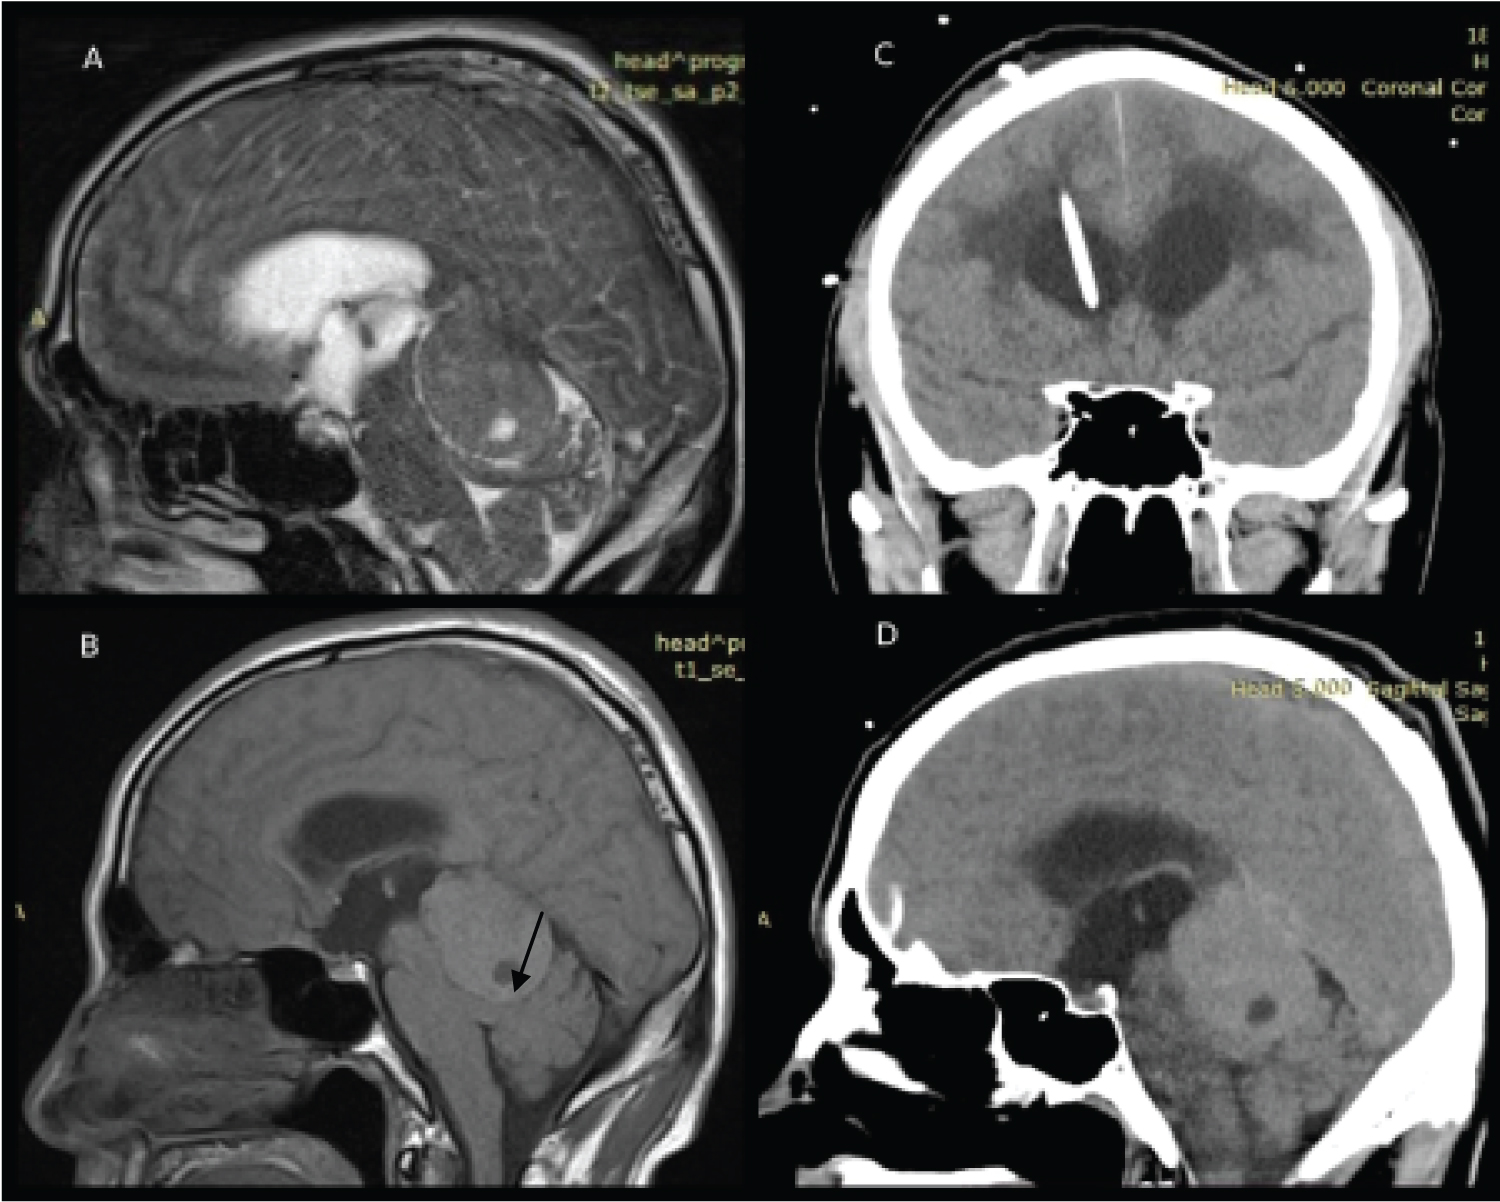

In this case report, we would like to present to you a 44-years-old man, with an initial complaint of hearing loss and inadequate behavior. According to his wife, he fell in April 2021 and afterward became strange and lost his ability to hear, he was emergently hospitalized in the district hospital, where he underwent magnetic resonance imaging (MRI), which showed a tentorial tumor with subtentorial growth, compressing the quadrigeminal plate and causing obstructive hydrocephalus by compressing aqueductus (Figure 1).

EVD was performed through right Kocher's point. The pressure was set at 15 cmH2O. CT scan after external ventricular drainage placement is shown in Figure 1C. To note he became less inadequate and aggressive after the first operation.

Figure 1: A) MRI shows encapsulated 4.25 × 3.15 × 2.89-cm in size tumor with hyper-signal intensity on T2WI, and heterogeneous slightly long/short signal on T1WI; B) The area of necrosis is also shown (arrow); C) Coronal CT scan of the patient after the placement of external ventricular drainage; D) Sagittal CT scan of the head showing solitary, irregularly contoured mass. To note, these CT scans were made 10 days later after the initial MRI scanning with signs of slight tumor increase. View Figure 1